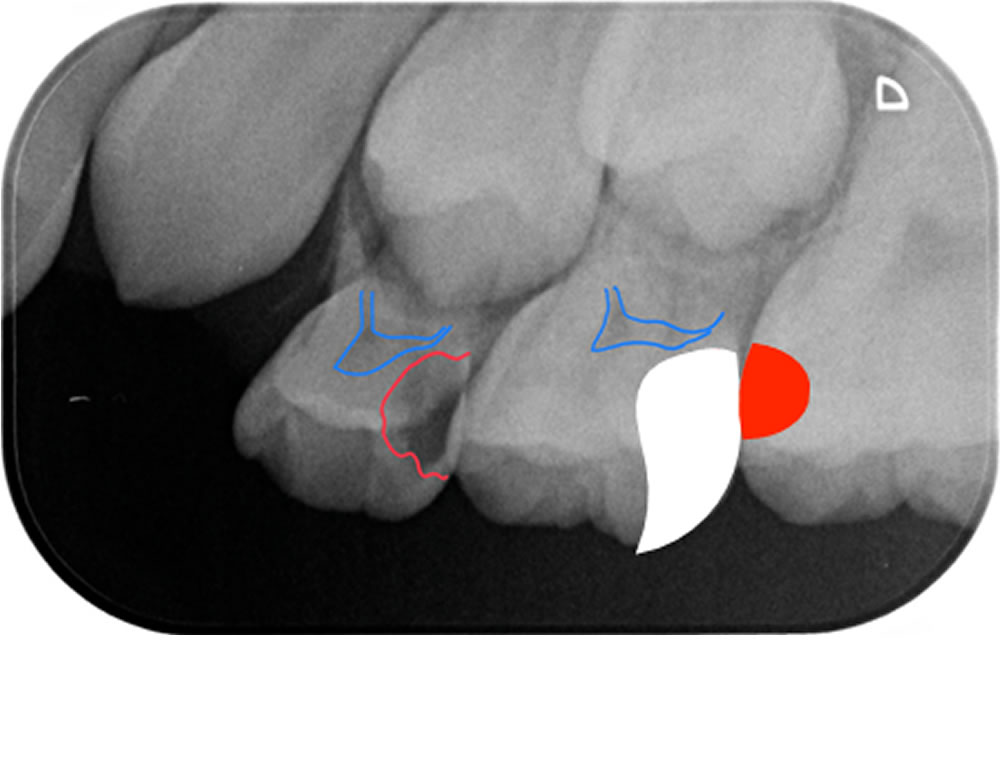

術前の写真です。左上6番近心、左上E(乳歯:5番)遠心、左上D(乳歯:4番)遠心部分は、象牙質に到達するむし歯が確認できました。(写真赤丸部)【※遠心:奥歯側 近心:前歯側】

付き添いで来られた親御さんにご了承いただき、レントゲン診査を行いました。レントゲンではむし歯の部分が黒く写ります。

診断および治療計画

左上D遠心、左上E遠心→C2(象牙質のむし歯)、コンポジットレジン充填(抜髄になる可能性あり)

両歯とも歯髄にかなり近いところまでむし歯が広がっています。むし歯を取り除くことで、神経の部屋まで到達した場合は、神経の治療に移行する可能性があります。むし歯を取り除き、神経まで到達はしなくても、術後の疼痛がひどい場合は神経の治療が必要になる可能性があります。

青点線:保存することができた健全歯質